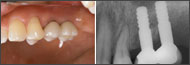

| 1ピースでの審美性の工夫(1) | |

| 植立直後の暫間被覆冠装着とその後のブラッシング | |

![]() ?上顎前歯2~2欠損の右上2,左上2に4LMを植立。植立直後にアルジネート印象を採り、翌日洗浄時までにTekを準備する。 |

![]() ?抜糸の2~3日後から術後用スーパーソフトブラシでブラッシングを再開、術後3~4週後には通常のブラシに戻って磨いてもらう。ブラッシングにより暫間被覆冠周囲の粘膜を十分引き締め、術後2ヵ月後に形成印象を行う。印象後はTek内外面に即重レジンを盛り、最終Crに近いTekの作成を心がける。 |

| 植立3Y後 | 最終TEKとBr装着 |

![]() ?Br装着。2004/08/30 |

![]() Br装着時の審美性を保っている。2007/05/09 |